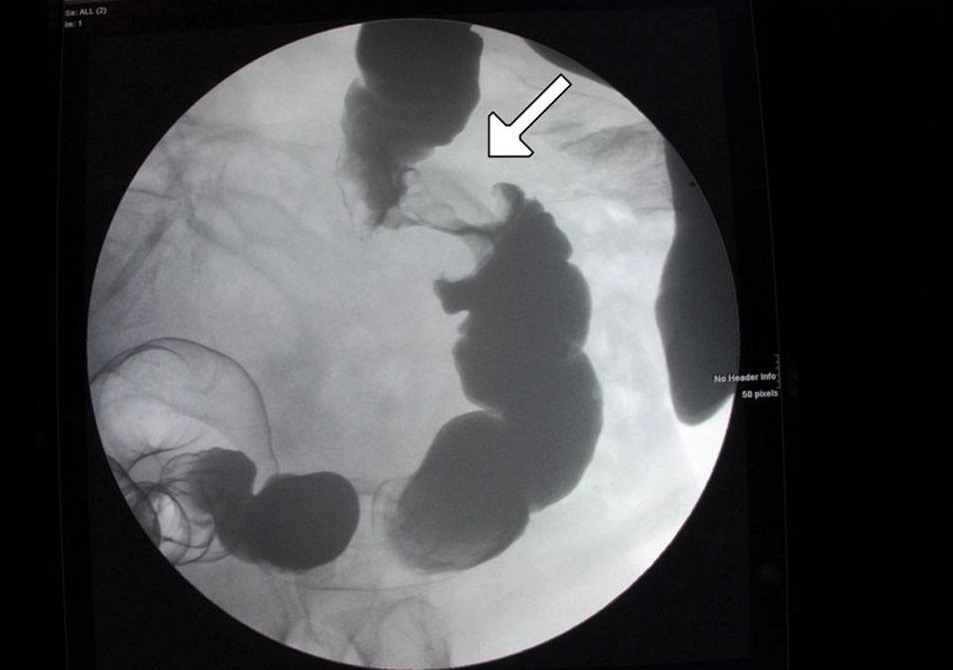

- Contrast radiography with enema (bird’s beak appearance in volvulus, Apple core sign in colonic malignancy)

Sigmoid volvulus

| Imaging |